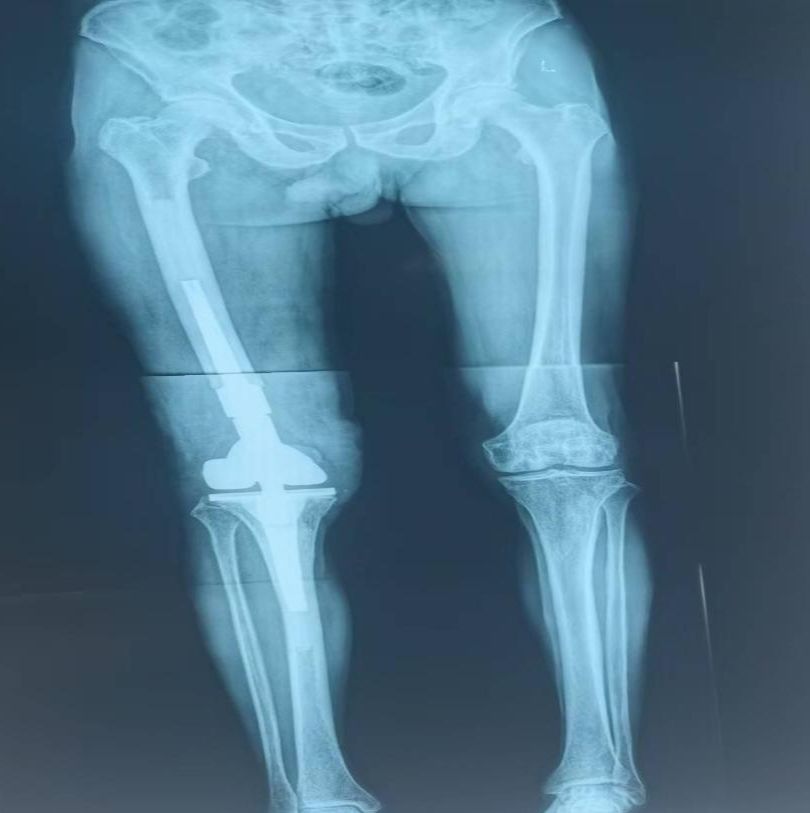

膝关节置换术后假体周围骨折,假体松动

膝关节置换术后假体周围骨折特殊假体返修术后

术后双下肢全长片